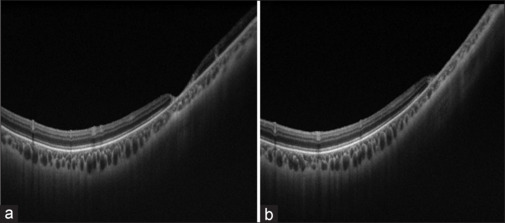

Methods: This is retrospective case series of CMV retinitis patients with known immunocompromised status and negative HIV results. Patients' data were reviewed for demographics, causes of the immunosuppressed status, concomitant systemic CMV infection, and its management. Ophthalmic findings included visual acuity (VA), anterior and posterior segments findings, CMV retinitis patterns and extensions, medications, number of intravitreal injections, fundus photographs, and CMV retinitis complications.

Results: During a study period of 2 years, 17 eyes of 9 patients were diagnosed with CMV retinitis with detected CMV in blood tests. Indolent granular retinitis pattern was found in 4 eyes (23.5%), and the fulminant necrotizing pattern in another 4 eyes (23.5%). In 1 eye (5.9%), frosted branch angiitis was observed. A mixed pattern between granular and necrotizing retinitis was seen in 4 eye (23.5%). The majority (n 11, 64.7%) of the affected eyes had an extensive retinal involvement (zone 1-3). Only two eyes had no macular involvement (11.8%). A large percentage of the included patients had controlled disease course with stable vision. Out of the studied 17 eyes, deterioration in terms of VA was seen in five eyes. In two patients, the disease course was complicated by vitreous hemorrhage.

Conclusion: In the majority of the patients with HIV-negative tests who received intravitreal and/or systemic anti-CMV medications, the clinical course of CMV retinitis was controlled with final stable vision.